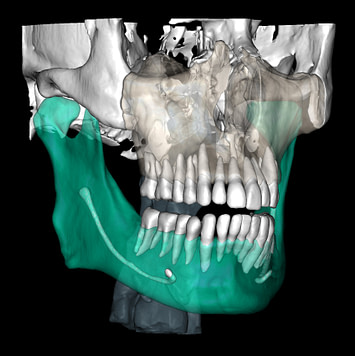

So what is Segmentation? It basically means taking the CBCT and delineating all the different 3D structures, bones, individual teeth, etc.

These can then be individually exported via the software by generating STL files from CBCT dicom data. This can be used in other dental software. Jaw STLs can be used in Modjaw (jaw motion capture) for TMJ analysis, for example. As well as in exocad to help visualize the jaws for surgical planning or guide creation.

Being able to take a DICOM file and turn it into STLs is useful for a host of different CAD/CAM indications.

CBCT Segmentation into STL

Generate STL files from CBCT DICOM data.

Generate maxilla and mandible in one STL file or face, teeth, maxilla, mandible, airway, cranial base, canals as separate STL files.